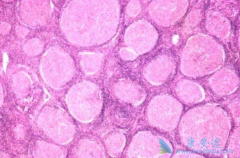

哪类的多发性骨髓瘤患者可以使用硼替佐米?

硼替佐米的适应症是哪些? 多发性骨髓瘤 :本品可联合美法仑和泼尼松(MP方案)用于既往未经治疗的且不适合大剂量化疗和骨髓抑制的多发性骨髓瘤患者的治疗;或单药用于多发性骨髓瘤患者最少接受过一种或者是一种以上治疗后复发。   套细胞淋巴瘤:本品 ...